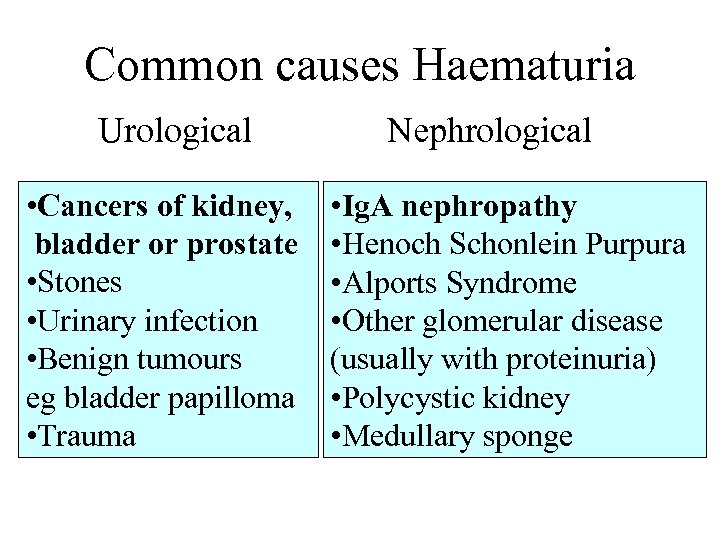

Common causes Haematuria Urological • Cancers of kidney, bladder or prostate • Stones • Urinary infection • Benign tumours eg bladder papilloma • Trauma Nephrological • Ig. A nephropathy • Henoch Schonlein Purpura • Alports Syndrome • Other glomerular disease (usually with proteinuria) • Polycystic kidney • Medullary sponge

Common causes Haematuria Urological • Cancers of kidney, bladder or prostate • Stones • Urinary infection • Benign tumours eg bladder papilloma • Trauma Nephrological • Ig. A nephropathy • Henoch Schonlein Purpura • Alports Syndrome • Other glomerular disease (usually with proteinuria) • Polycystic kidney • Medullary sponge